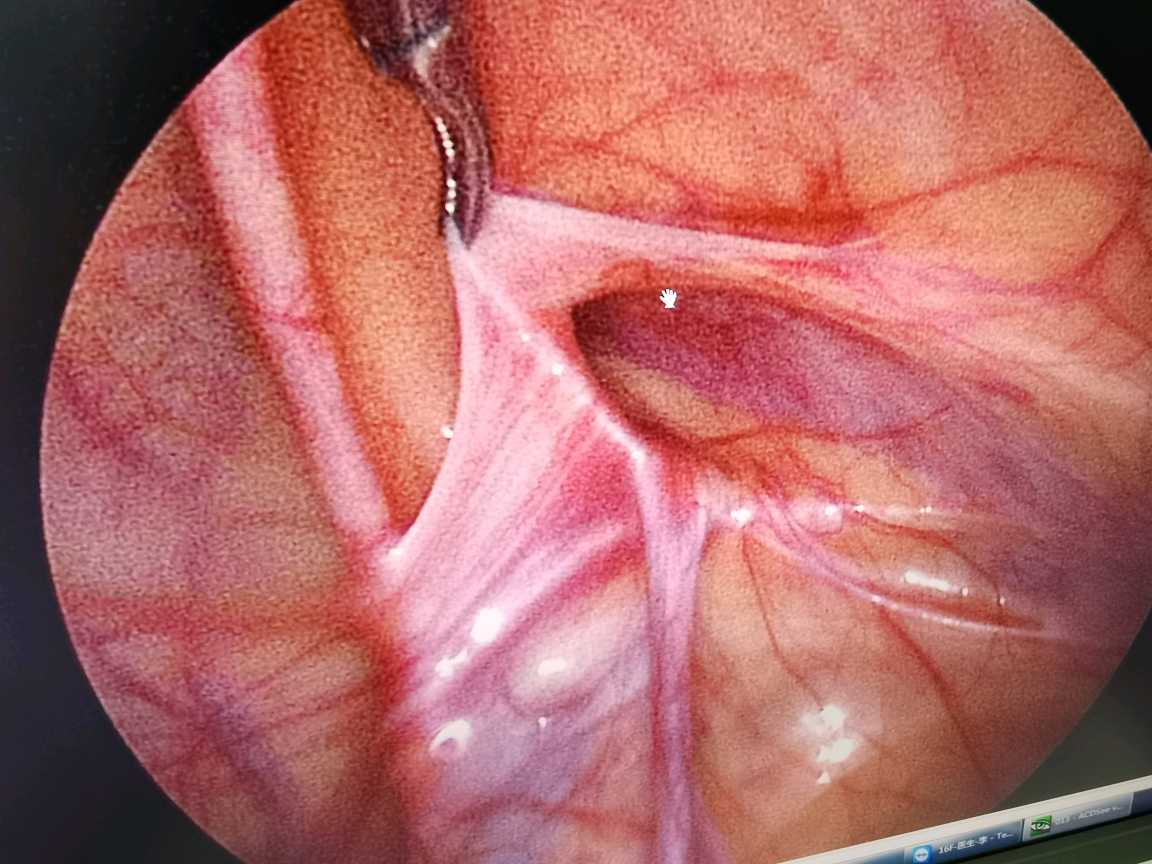

教科书上明确指出:因腹股沟斜疝容易嵌顿,腹股沟疝一经诊断后,应尽早进行手术治疗,以免发生嵌顿疝导致严重后果。手术治疗腹股沟疝已相当安全,可不受年龄限制。我科曾成功对出生7天宝宝的腹股沟斜疝进行腹腔镜手术(因腹股沟斜疝嵌顿)。腹腔镜下疝囊高位结扎术在我国技术成熟,其优点为术中精索损伤小、术后切口小,另外腹腔镜可以探查到对侧内环口未闭合时同时给予预防性结扎,传统开刀手术存在对侧再发需再次手术可能。

腹腔镜下内环口高位结扎